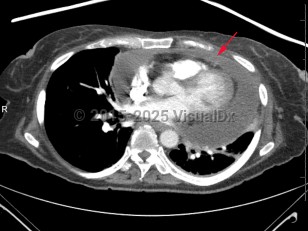

Cardiac tamponade is a true life-threatening medical emergency that is fortunately treatable with prompt diagnosis and treatment. Tamponade is a form of obstructive shock caused by elevated intrapericardial pressure that results in decreased cardiac filling and subsequent decreased cardiac output. Normally, the pericardium lacks compliance, and thus even a small increase in pericardial fluid can cause a rapid rise in pericardial pressure. If the pressure rises higher than the right-sided cardiac pressure, it causes decreased cardiac filling, ventricular interdependence, obstructive shock, and if untreated, cardiac arrest.

When intrapericardial pressure rises, it may yield in reduced cardiac filling secondary to changes in the right atrial-to-systemic venous pressure gradient. In severe cases, cardiac output is reduced to such an extent that the body is unable to maintain adequate systemic and coronary artery perfusion. Untreated, this leads to cardiovascular collapse and death.

All patients with pericardial effusions are at risk for tamponade. The causes of pericardial effusions are many and varied. They include, but are not limited to, trauma, malignancy, metabolic abnormalities (including uremia), pericarditis, tuberculosis, hypothyroidism, dissection, myocardial infarction, and iatrogenic injuries. Rapidly accumulating effusions pose a greater risk than do slower growing effusions.